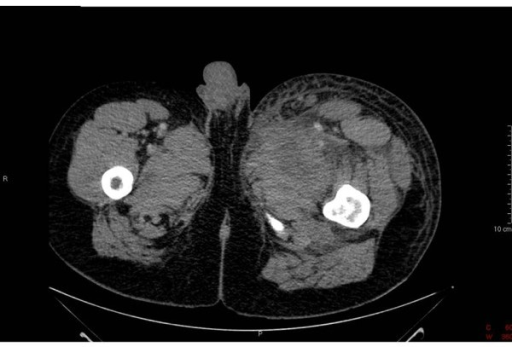

- 호흡기 탄저병: 초기에는 감기와 유사하지만, 며칠 후 심각한 호흡곤란과 쇼크로 이어진다. 치사율이 매우 높지만(약 97%),[131] 자주 발생하지는 않는다. 흡입성 탄저병은 보통 노출 후 1주일 이내에 발생하지만 최대 2개월까지 걸릴 수 있다.[25] 폐 자체보다는 먼저 흉부의 림프절을 감염시키며, 출혈성 종격동염을 유발하여 흉강에 혈성 액체가 축적되어 숨가쁨을 유발한다.